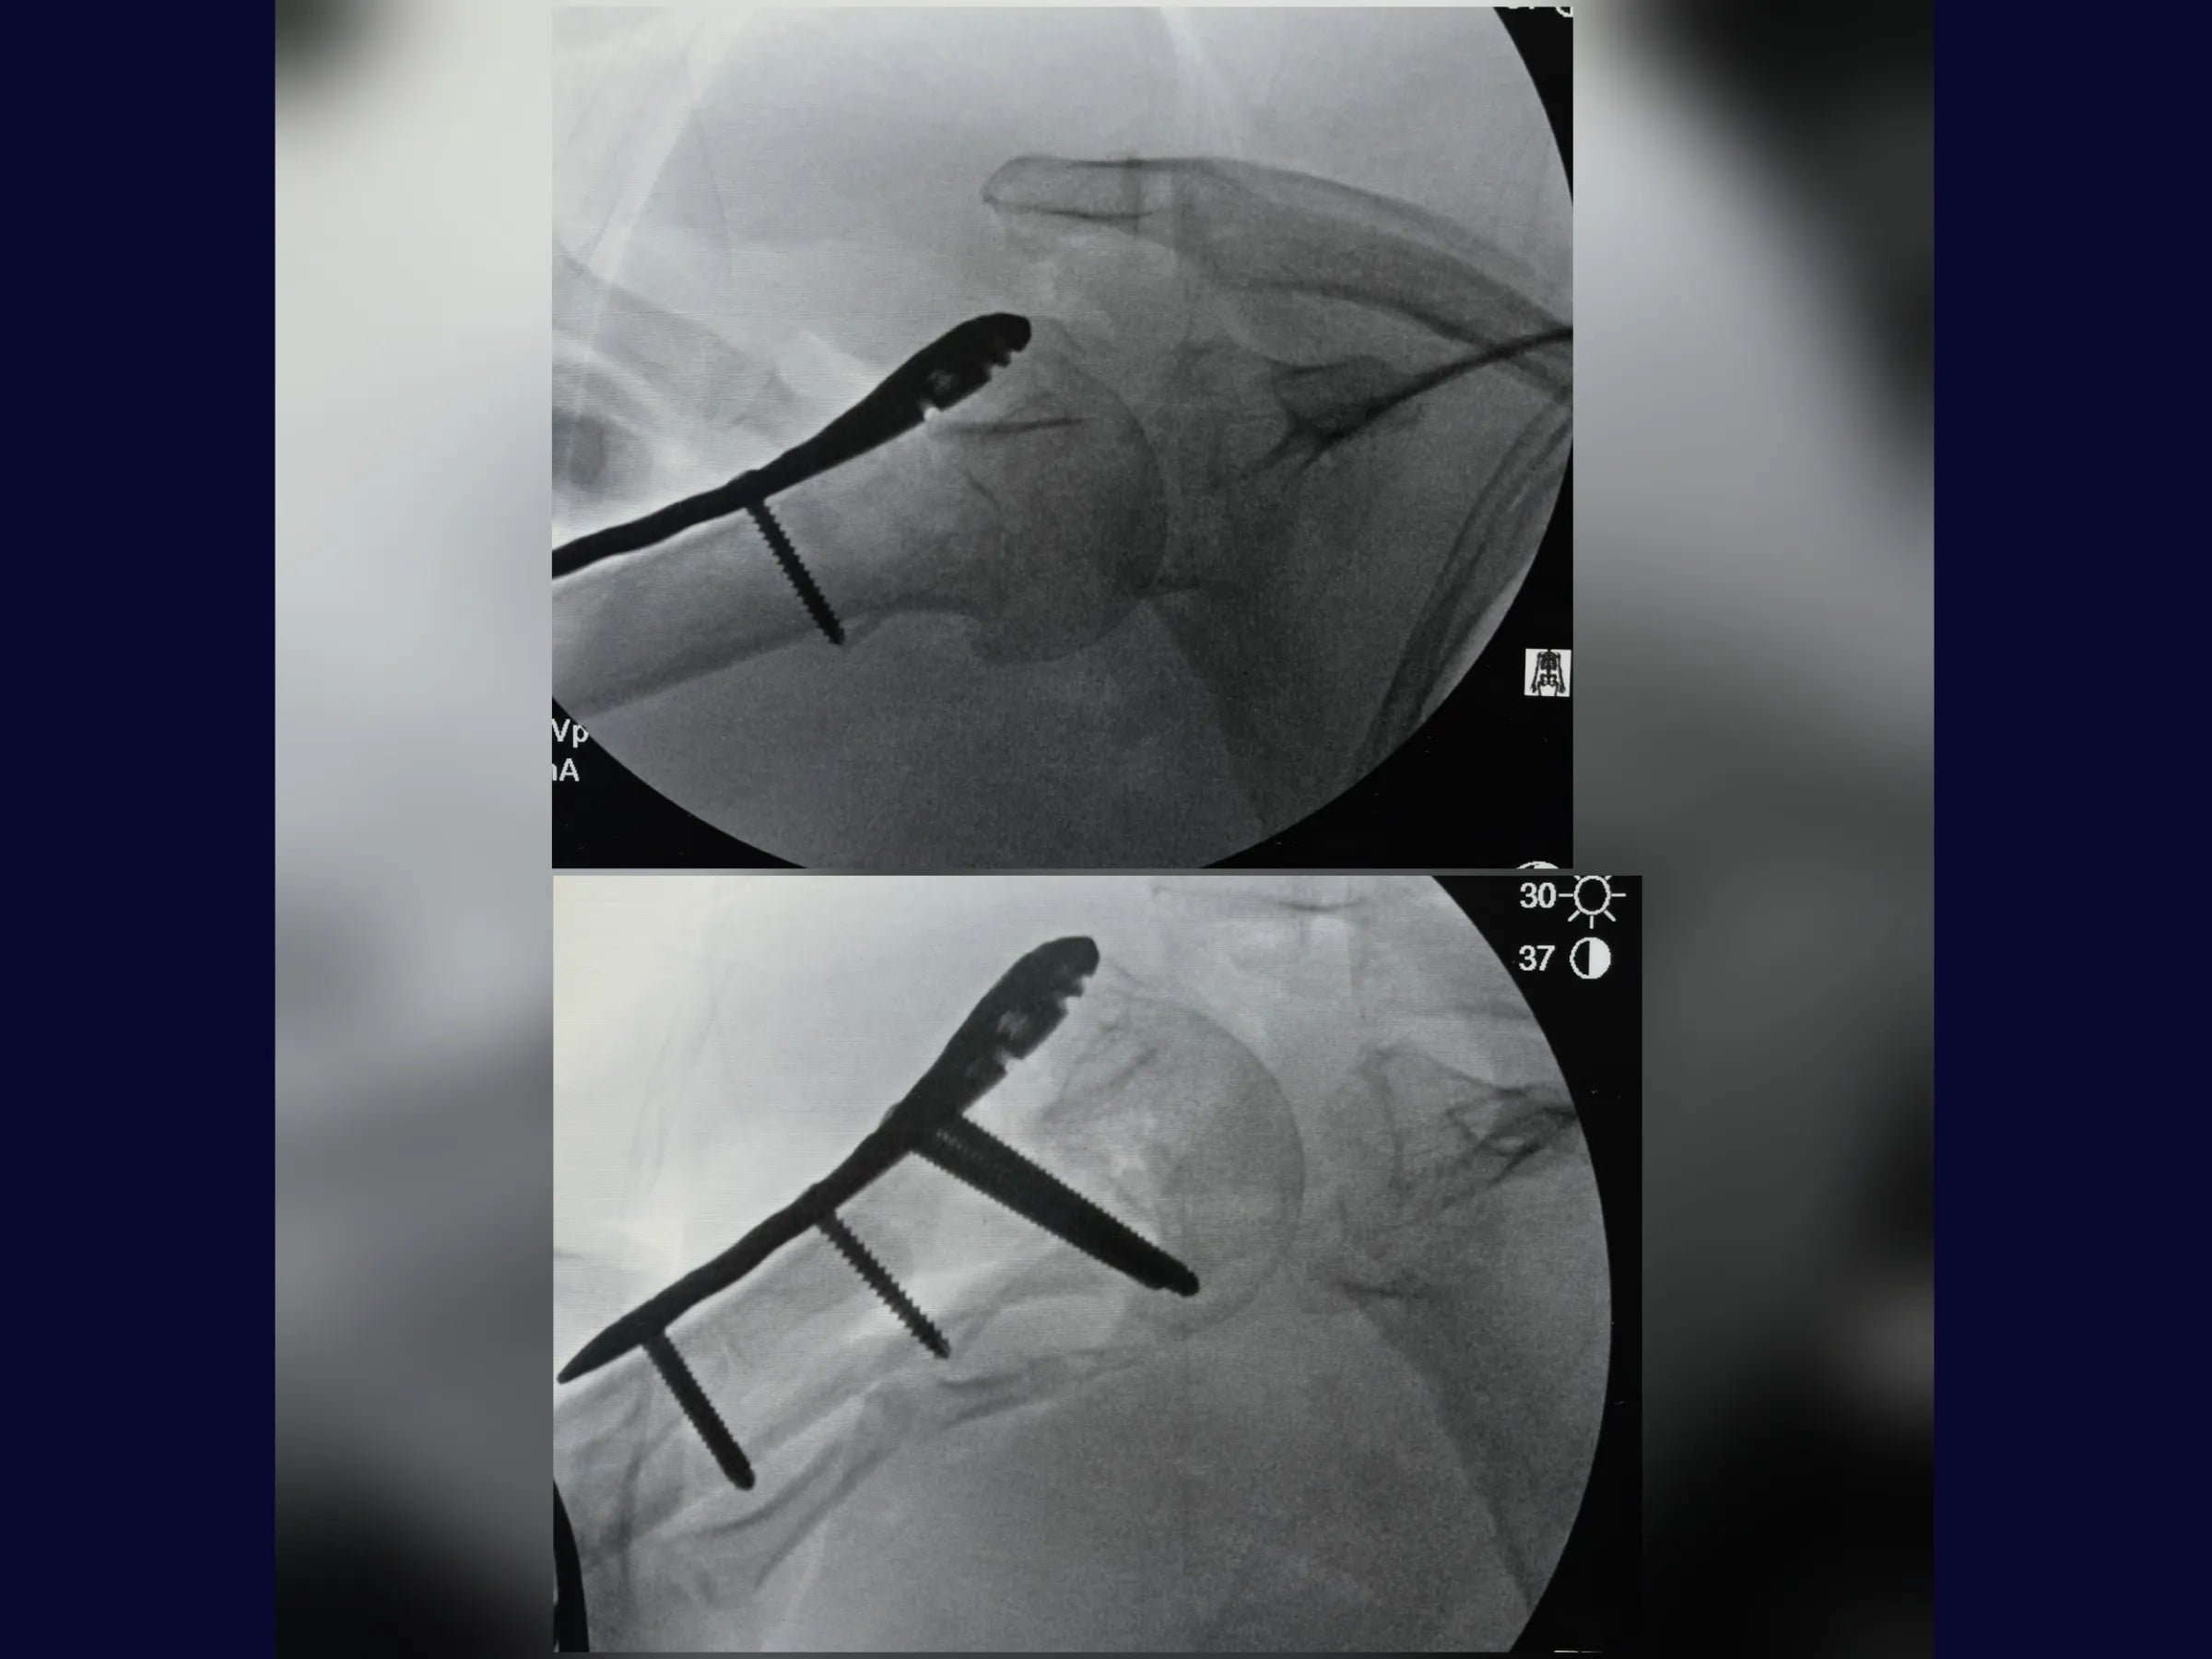

- Controle Radiográfico e Ajustes Finais: Correção de cisalhamento e simetria com reposicionamento de parafusos.